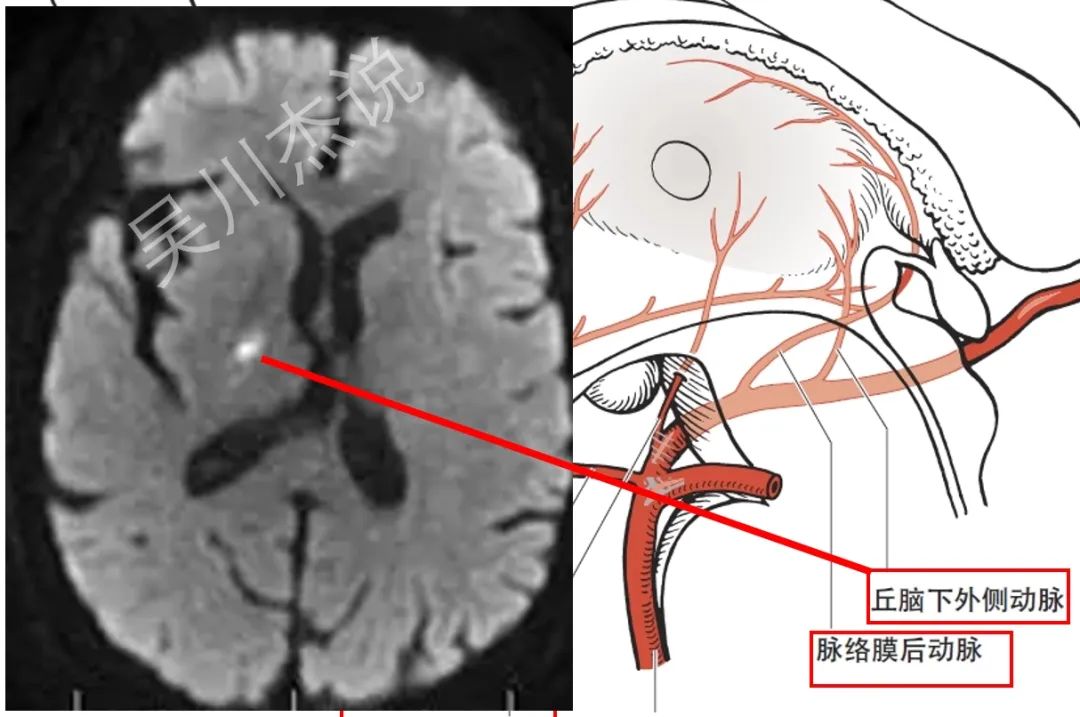

• 丘脑下外侧动脉:又称丘脑膝状体动脉,起自大脑后动脉P2段。朋友们,抛弃这个难以记忆的丘脑膝状体动脉的称呼,丘脑下外侧动脉当然是供应丘脑的下外侧部分了。

• 脉络膜后动脉:起自大脑后动脉P2段。貌似最后丘脑大概南极位置的血供就只剩下脉络膜后动脉来供应了吧。

放大一点,我们再来看看上图中这4根动脉的供血范围。

我们再来看看一个立体的模式图,从另外一个角度再来理解一下这四根动脉的起源、走形和分布。